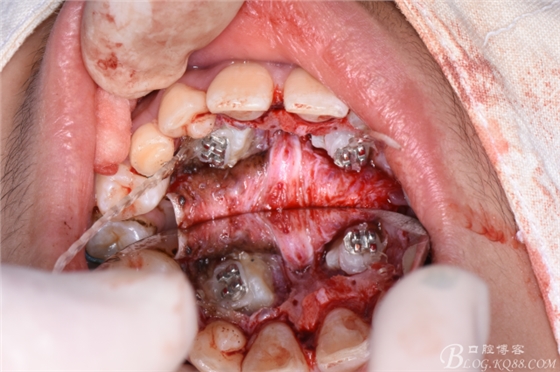

圖12.修整完成后的13、23牙冠暴露情況

圖13.光固化粘接23托槽

圖14.分別在13、23牙冠上粘接帶有橡皮鏈的托槽